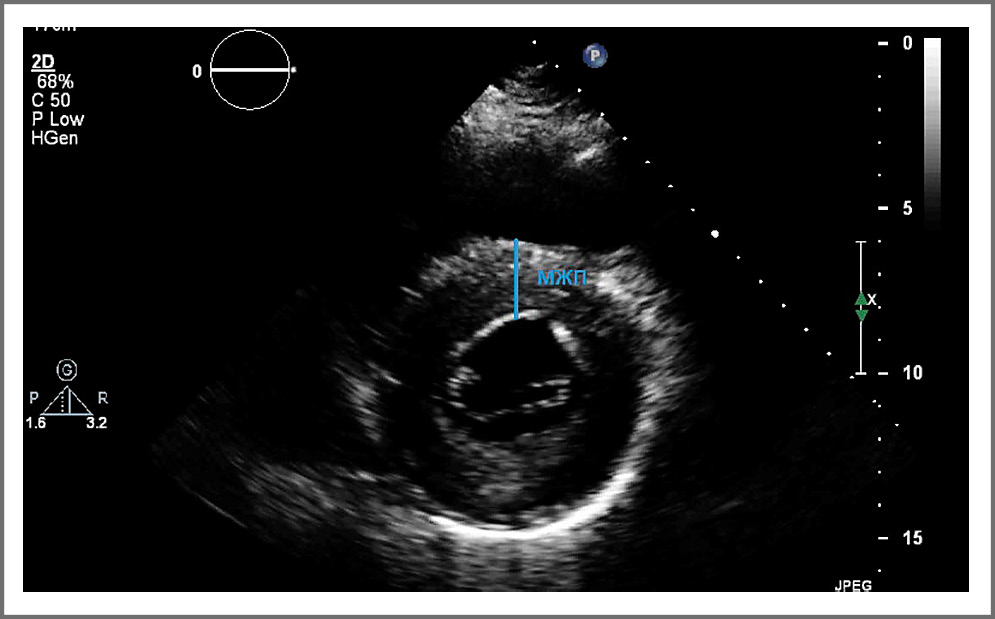

При измерении из парастернального доступа в позиции по длинной оси ЛЖ необходимо оценить соотношение поперечного размера аорты и ЛП, толщину межжелудочковой перегородки, конечно-диастолический и конечно-систолический размеры ЛЖ, толщину задней стенки (рис. 2). Измерение толщины межжелудочковой перегородки может быть затруднено из-за таких структур ПЖ, как трабекулы, наджелудочковый гребень и модераторный пучок. Толщина стенки может быть проверена дополнительно в парастернальной позиции по короткой оси (рис. 3).

Рис. 3. Оценка толщины межжелудочковой перегородки из парастернального доступа в позиции по короткой оси.